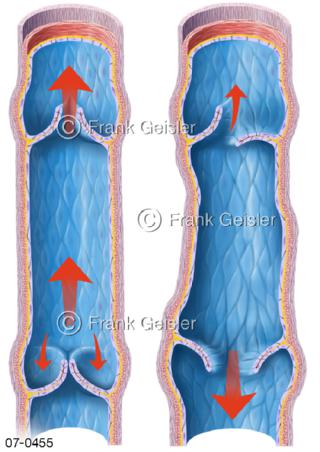

Bildergalerie Herz, Blutkreislauf

Bilder zu Herz, ein muskuläres Hohlorgan, das den menschlichen Körper durch rhythmische Kontraktionen mit Blut versorgt und dadurch die Durchblutung der Organe sichert, das Kreislaufsystem zeigt den Transport von arteriellem sowie venösem Blut durch das kardiovaskuläre System (Herz-Kreislauf-System), bestehend aus Blutgefäßen, Lymphgefäßen und dem Herz